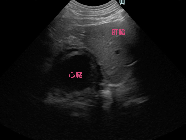

エコー検査、CT検査にて胸腔内(心臓尾側)に肝臓実質(方形葉)が脱出。